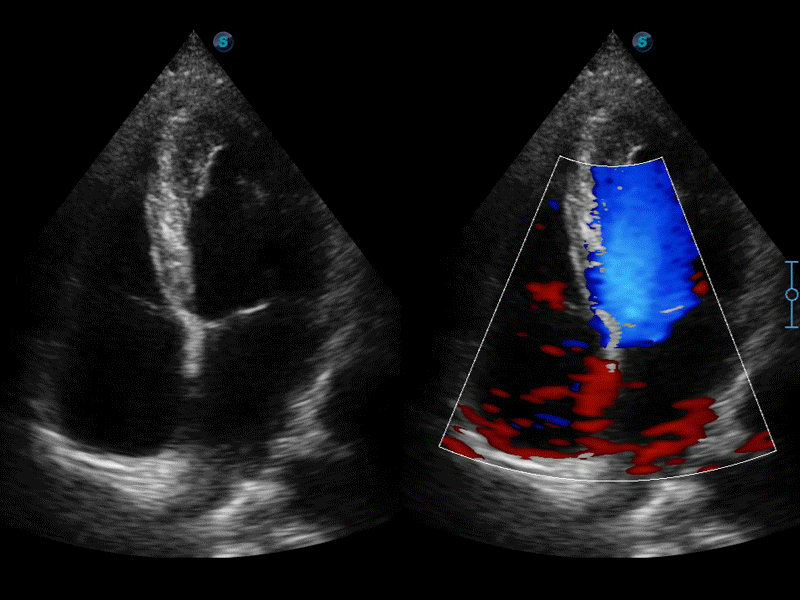

高分辨率血流成像技術提高了對低速血流信號的檢測能力。在提高空間分辨率的同時,也克服了血流外溢現(xiàn)象,為用戶提供更加真實的血流動力學信息。